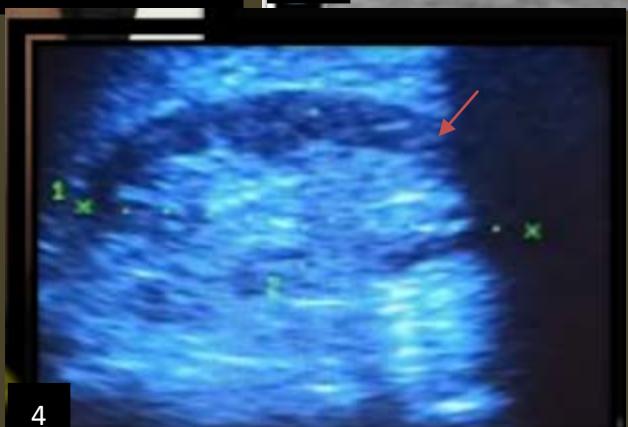

Iconography C: lower left renal polar cystic lesion, alcoholic. Image 1. showing an echo-empty (cystic) left lower renal polar mass,2. CT image showing a left lower polar hypodense mass 3. Ultra sonographic image in B mode showing subcutaneous anesthetic infiltration,4. Image of the left kidney in mode 12 months after sclerotherapy, 5. Image of a clear liquid that had been removed during sclerotherapy.